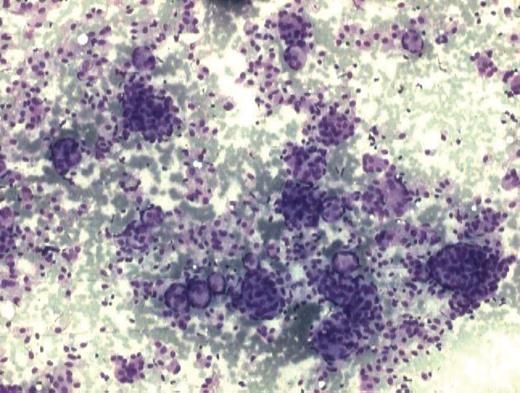

An 18-year-old female presented with a complaint of swelling below the angle of mandible on the right side which was associated with difficulty in swallowing since the last 3 months. Local examination revealed a swelling measuring 1.5 × 1 cm which was firm, fixed, non-pulsatile, non-transilluminant and non-tender. Oral cavity examination revealed a swelling of ∼1.5 cm diameter seen on the right side of the oropharynx. Computer tomography (CT) revealed that swelling is due to a heterogenous enhancing mass in parapharyngeal space with foci of calcification. The mass was not having any intracranial extension. The patient was subjected to fine needle aspiration cytology (FNAC) and the aspiration from the swelling yielded very low cellularity. A repeat FNAC with an intraoral approach was performed. Smears revealed loose cohesive clusters of cells in syncytial fragments along with concentric whorling pattern at places (Fig. 1). These cells were oval-to-spindle shaped with elongated nuclei having bland nuclear chromatin. At places, these cells had palisaded appearance with fibrillary pink substance. Singly scattered cells and myxoid substance were also observed in the haemorrhagic background. Occasional psamomma bodies were also discerned at places in the smears (Fig. 2). A cytological diagnosis of spindle cell lesion of neural origin with the closest resemblance of ectopic meningioma was rendered. The tumour was excised and subjected to histopathological examination. Microscopically, tumour was composed of oval-to-spindle cells with indistinct outline and eosinophilic cytoplasm. The nuclei were round to oval with homogenous chromatin. No mitosis was observed. In some areas, cells were arranged in whorling pattern. Numerous psamomma bodies were also noted (Fig. 3). The cytological diagnosis of extracranial meningioma was confirmed on histopathology. The patient is on regular follow-up without any complication.

Smear showing occasional psamomma body in between cluster of cells. (MGG ×200).